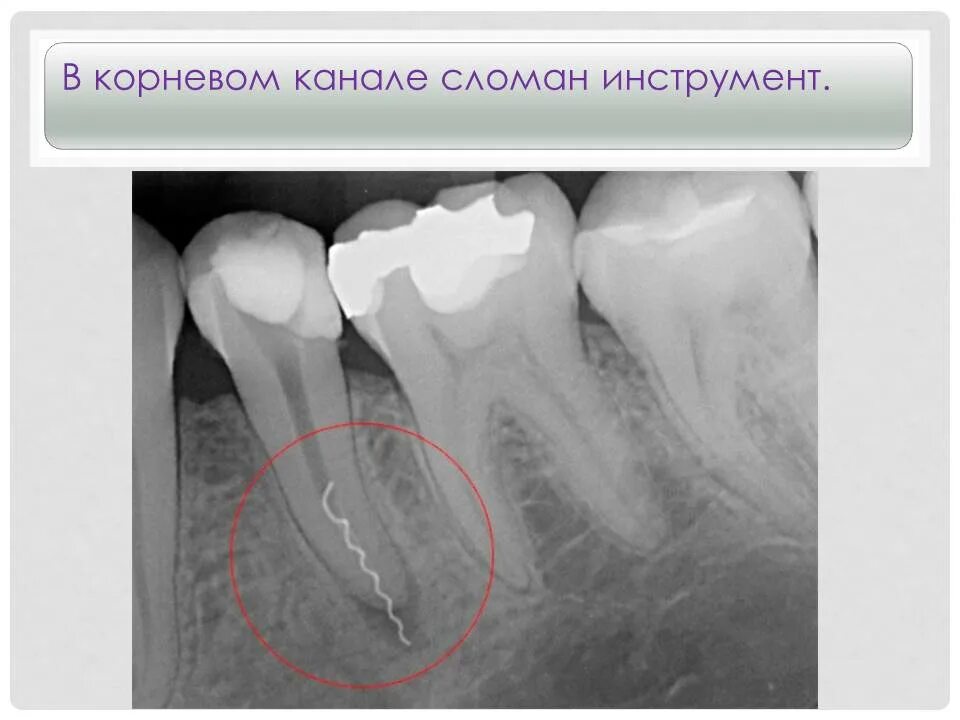

Перелечивание каналов зуба. пломбировочный материал вышел за пределы канала зуба. если перелечить каналы зуба.